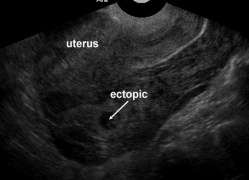

Ectopic pregnancy

- Implantation of blastocyst outside of endometrium

- Occur in fallopian tubes, cervix, ovaries, peritoneal cavity, or scar of prior uterine surgery

- Most definitive sonographic sign is gestational sac with yolk sac, embryo, or fetal heart beat outside of the endometrium

- Tubal pregnancy

- "Tubal ring" sign: echogenic thick-walled anechoic sac visualized between uterus and ovary (separate from ovary when pressure applied to fallopian tube with probe)

Ectopic pregnancy

Ectopic pregnancy Free fluid in cul-de-sac with no gestational sac visualized in uterus

Free fluid in cul-de-sac with no gestational sac visualized in uterus Ectopic pregnancy between ovary and uterus, suggestive of tubal ectopic